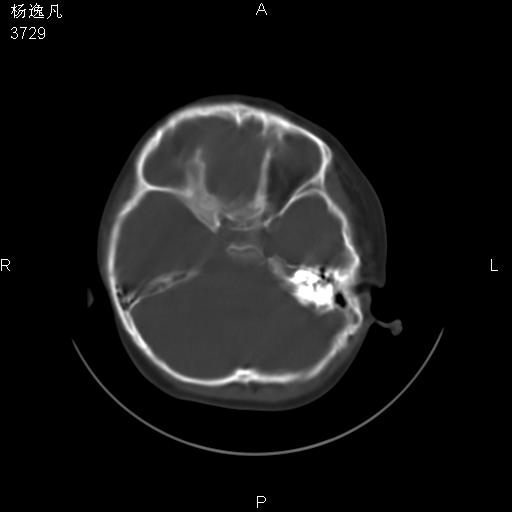

男性,5岁,面部受外伤,余无特殊

骨窗

位置太不标准了!

双侧位置太不对称,未见明显骨折征象。

谢谢各位的意见,发的都是些常见的,扫描位置不好,患者不合作,折腾了好久,容易么